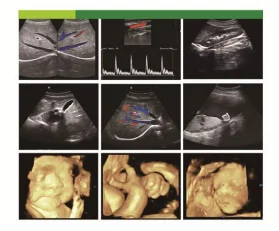

Product name | Medical Ultrasound Equipment |

Display | 15inch LCD display |

Probe | Convex,Linear,Vaginal,Rectal,Micro-convex |